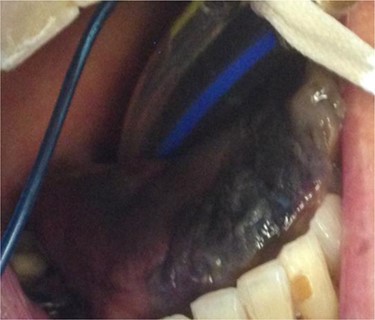

At 12 months review, the dorsum of the tongue had healed with considerable scarring (Fig. 3). Despite the significant restriction in tongue movement and speech deficit, the patient however declined further surgical intervention.